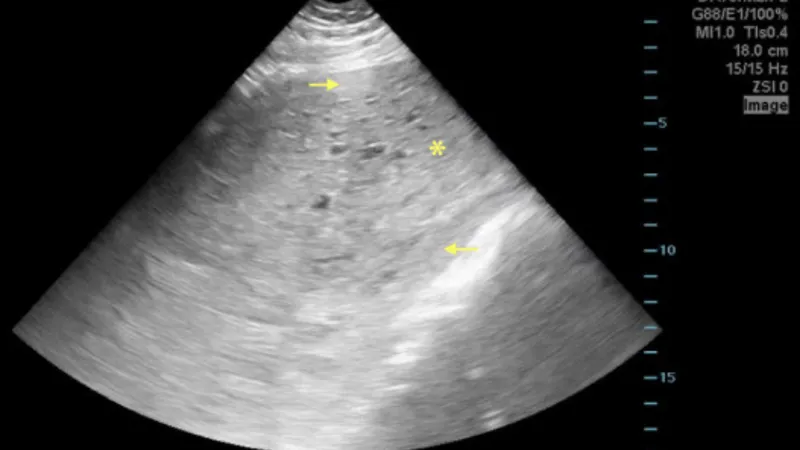

- Pelvic ultrasound: Provides an initial look at uterine size, structure, and the presence of masses or ovarian abnormalities.